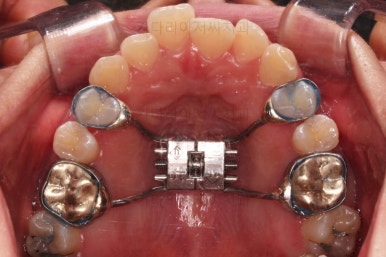

부산안면비대칭 첫 단꼐로 악궁확장 장치를 했어요.

비대칭이 있어서 한 것도 아니고, 공간이 부족해서 한 것도 아니에요.

비발치로 하고자 해서 한 것도 아니에요.

단순히 위아래의 조화가 안맞을 때 하는 것이 악궁확장이며 이번 환자분도 위아래의 조화가 안맞아서 악궁확장장치를 사용했고, 그 근거는 CT 분석을 통해서 이루어져요.

악궁확장 이후에 교정장치를 부착하고 치열을 가지런하게 해줘요.